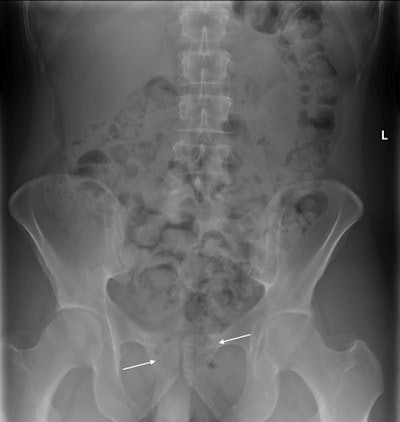

Plain x-ray of a suspected drug smuggler, who later passed two large, regularly oval, 50 x 35-mm hard plastic containers containing illegal substances. The containers are located in the rectum between the arrows. It can be difficult to distinguish them from stool. Image courtesy of Dr. Markus Sormaala.He thinks there is an urgent need for radiologists to accurately identify drugs in the GI tract. False-negative interpretations may result in a trafficker getting released and the illegal substance ending up on the black market, while false-positive interpretations result in innocent people being detained, which causes expensive and embarrassing delays and poses ethical problems.

Illegal drugs in the GI tract can cause bowel obstruction or intoxication due to ruptured drug packets in the bowel. Cocaine, heroin, LSD, and other illegal substances in pill form are typically swallowed or passed into the colon per rectum, the authors noted. Heroin and cocaine are mostly wrapped in plastic or condoms, to form 2- to 4-cm packages, which are then swallowed. A mule can often store up to 100 packages in their colon and small intestine. Another method is to put drugs into larger 4- to 6-cm hard plastic containers, which are then placed into the rectum. These containers can hold solid drugs, powder, or pills.

"A large amount of stool in the bowel can be misinterpreted as illegal substances," they noted. "Advised wrapping techniques and a gasless abdomen can make detection of the packages difficult. As only a fraction of the negatively interpreted cases can be verified, it is possible that false-negative interpretations are common."